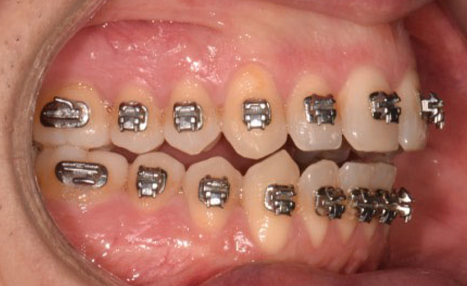

To achieve these goals, the Damon Ultima system was selected for its precision in torque control and its capacity for individualized bracket selection. A Smile Arc Protection (SAP) strategy guided bracket placement from the start, combined with careful archwire sequencing and progressive mechanics.

From the outset, bracket placement was the cornerstone of the treatment strategy. The upper central incisors were bonded 1–1.5 mm more gingivally than the canines, with laterals slightly lower, to recreate a natural curvature and protect the smile arc. Variable torque brackets were selected individually for each anterior tooth, according to its specific requirements. This feature of the Damon Ultima system represents a significant advantage: it combines the low-friction benefits of self-ligation with earlier expression of anterior torque. When paired with the rapid arch development characteristic of the system, this approach allows for the ideal torque to be achieved very early in treatment. As a result, proclination of the incisors is effectively avoided while maintaining efficient alignment.

The initial alignment was performed with light CuNiTi archwires, promoting gradual expansion and alignment while avoiding heavy forces. Progressively, the treatment advanced to the final 0.018 x 0.0275 stainless steel archwires, ensuring full torque expression and establishing control over the occlusal plane.

Given the patient’s vertical pattern and open bite tendency, posterior bite turbos were incorporated early to control extrusion and stabilize the vertical dimension. As treatment progressed, refinements included rebonding the upper anterior brackets to fine-tune torque and smile arc display. Crossbite elastics were also introduced to correct the transverse discrepancy in a controlled manner.